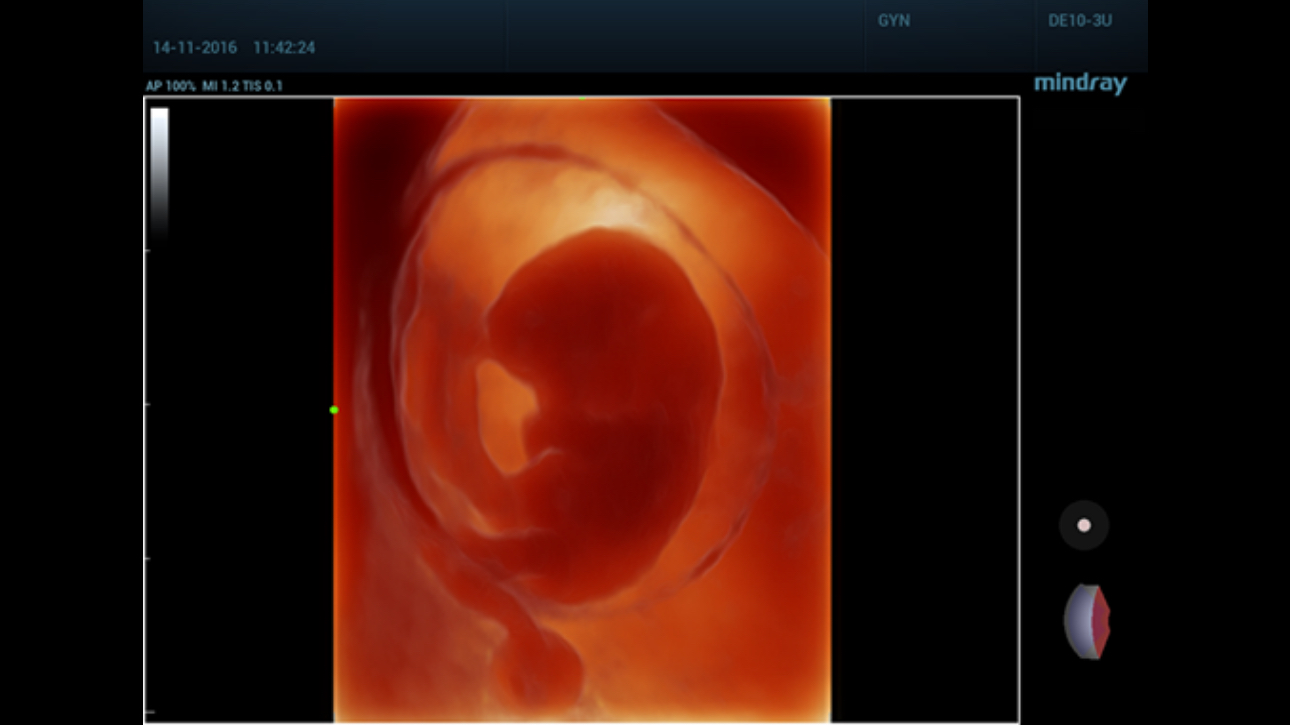

Comprehensive upgrading on iLive to significantly improve the detailed resolution as well as anatomical realism. Hyaline is a new rendering method that dynamically applies transparency to rendered structures for a more comprehensive view of anatomy, therefore better displaying internal anatomy from a solid surface.